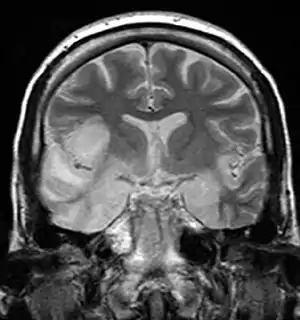

Herpesviral encephalitis and herpesviral meningitis Herpes simplex encephalitis (HSE) is a rare life-threatening condition that is thought to be caused by the transmission of HSV-1 either from the nasal cavity to the brain's temporal lobe or from a peripheral site on the face, along the trigeminal nerve axon, to the brainstem.[17][18][19][20] Despite its low incidence, HSE is the most common sporadic fatal encephalitis worldwide. HSV-2 is the most common cause of Mollaret's meningitis, a type of recurrent viral meningitis.